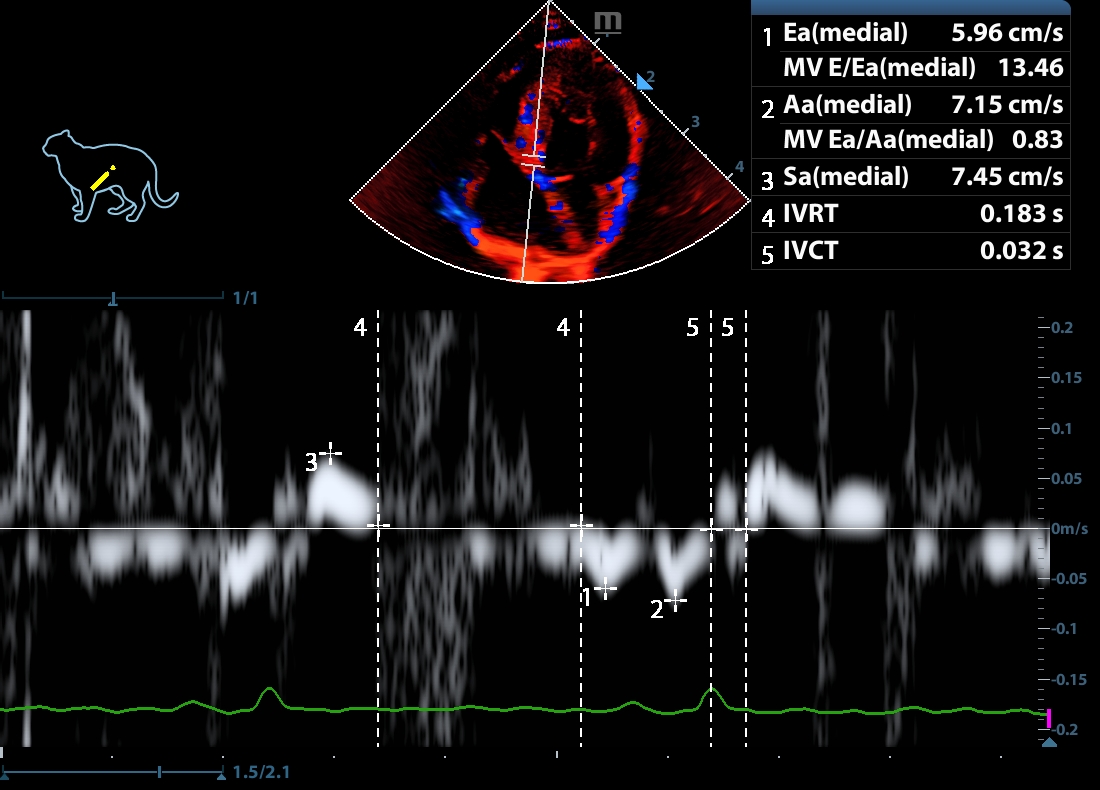

202505170045570152CARD.JPG